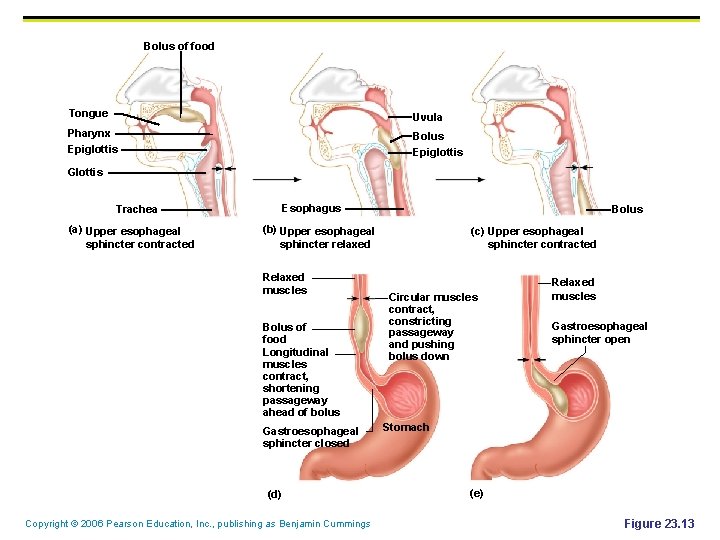

Digestive Processes in the Mouth § Food is ingested § Mechanical digestion begins (chewing) § Propulsion is initiated by swallowing § The pharynx and esophagus serve as conduits to pass food from the mouth to the stomach Copyright © 2006 Pearson Education, Inc. , publishing as Benjamin Cummings

Bolus of food Tongue Uvula Pharynx Epiglottis Bolus Epiglottis Glottis Esophagus Trachea (a) Upper esophageal sphincter contracted Bolus (b) Upper esophageal sphincter relaxed Relaxed muscles Bolus of food Longitudinal muscles contract, shortening passageway ahead of bolus Gastroesophageal sphincter closed (d) Copyright © 2006 Pearson Education, Inc. , publishing as Benjamin Cummings (c) Upper esophageal sphincter contracted Circular muscles contract, constricting passageway and pushing bolus down Relaxed muscles Gastroesophageal sphincter open Stomach (e) Figure 23. 13